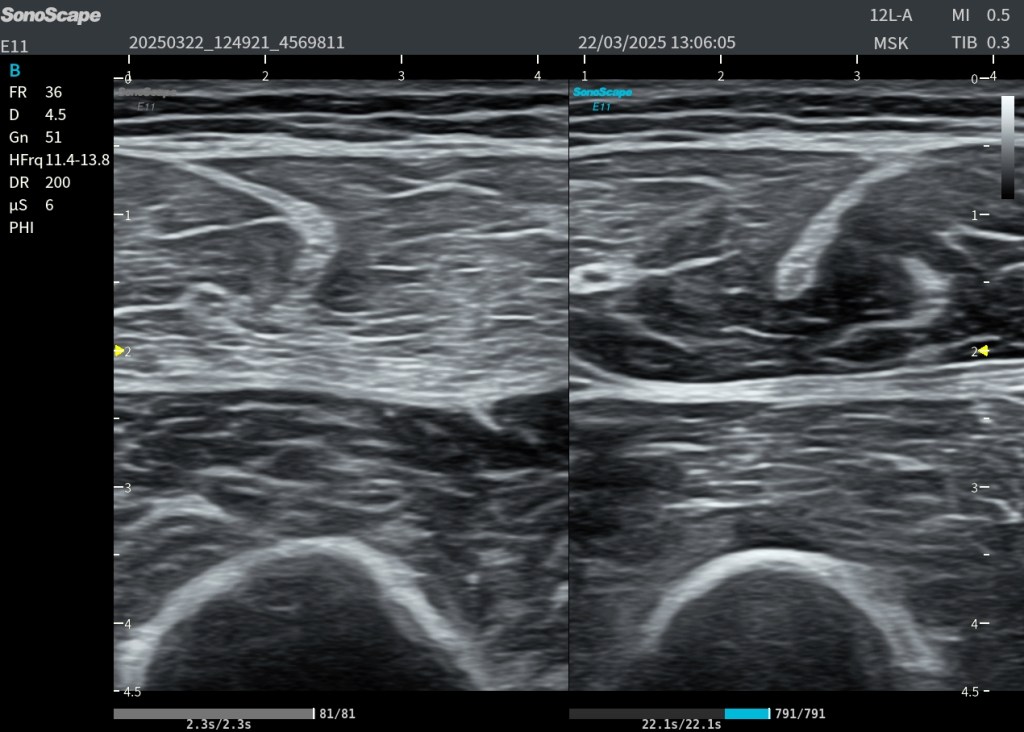

La exploración ecográfica de la planta del pie, es compleja, multitud de estructuras en muy poco espacio, pero debe tener y tiene. en mi opinión un punto de partida muy claro: el reconocimiento del plano muscular superficial y la progresión ordenada hacia los planos profundos. Las imágenes mostradas representan exactamente ese recorrido, combinando un corte transversal con su correlación en longitudinal, lo que permite entender una ecoestructura básica y músculo vascular, como punto de partida de la exploración de la planta del pie.

En el corte transversal, la primera estructura que aparece de forma constante es el flexor corto de los dedos (1). Se presenta como una masa muscular hipoecoica con un patrón fibrilar interno, reconocible por su tamaño, que ocupa prácticamente todo el plano superficial. Este músculo no solo es fácil de identificar, sino que actúa como una auténtica “puerta de entrada” a la anatomía plantar: si no lo reconoces con claridad, es muy probable que estés fuera de plano.

Justo por debajo de este músculo aparece una estructura mucho más brillante, lineal, que contrasta claramente con el tejido muscular: la aponeurosis del flexor largo de los dedos (2). Ecográficamente, su aspecto hiperecogénico y continuo la delata como una estructura tendinosa/aponeurótica. Esta línea no solo separa planos, sino que marca el paso hacia una anatomía más compleja y profunda.

Al atravesar esta referencia, entramos en el territorio del cuadrado plantar (3). A diferencia del plano superficial, aquí el patrón muscular es más compacto, homogéneo y menos organizado visualmente, lo que puede generar dudas si no se conoce bien la anatomía. Este músculo, profundo y funcionalmente ligado al flexor largo de los dedos, es clave porque nos sitúa justo encima del plano vascular.

En este mismo nivel profundo, y con una disposición característica, aparece el tendón del peroneo largo (4). Su identificación es especialmente importante: se observa como una estructura claramente fibrilar, hiperecogénica y bien delimitada, con un trayecto oblicuo que rompe la simetría del resto de estructuras. Este tendón es una referencia anatómica de enorme valor, porque confirma que estamos en el plano correcto y orientados adecuadamente dentro del mediopié.

Finalmente, en el nivel más profundo de la imagen, aparece la estructura que da sentido a toda esta organización: el arco plantar profundo (5). En modo B puede pasar desapercibido o verse de forma incompleta, pero con Doppler se revela como una estructura vascular bien definida. No es un vaso aislado, sino una anastomosis arterial que representa el eje vascular plantar profundo.

Cuando pasamos a la imagen en plano longitudinal, toda esta anatomía se reorganiza y cobra aún más sentido. El flexor corto de los dedos (1) se transforma en una estructura alargada, donde su patrón fibrilar se hace más evidente y continuo. El cuadrado plantar (3) se observa como un plano muscular profundo más compacto, mientras que el tendón del peroneo largo (4) destaca claramente por su morfología lineal y su continuidad, facilitando su seguimiento dinámico. La aponeurosis, aunque más sutil, sigue actuando como una línea de separación entre planos.

Pero hay un elemento especialmente relevante desde el punto de vista anatómico y ecográfico: el llamado triángulo arterial plantar. Este concepto, que se aprecia especialmente en la imagen con Doppler, está formado por la arteria plantar medial, la arteria plantar lateral y el propio arco plantar profundo. Más que una figura geométrica estricta, es una forma de entender la disposición vascular en este plano. Identificar este triángulo significa que estás exactamente donde debes estar.

Fíjate en los pictogramas, en las referencias musculares y vasculares, usa el Doppler, te recomiendo el Power, por su mayor sensibilidad y parte desde un punto de partida con la anatomía estudiada. Desde el punto de vista práctico, este conjunto de referencias permite algo fundamental: Orientarse. La ecografía plantar no consiste en reconocer estructuras aisladas, sino en entender cómo se relacionan entre sí en profundidad. El músculo superficial te introduce, la aponeurosis te guía, el cuadrado plantar te posiciona, el tendón peroneo largo te confirma y el arco plantar profundo te valida y desde ahí seguiremos estudiando el pie, en próximos Post.